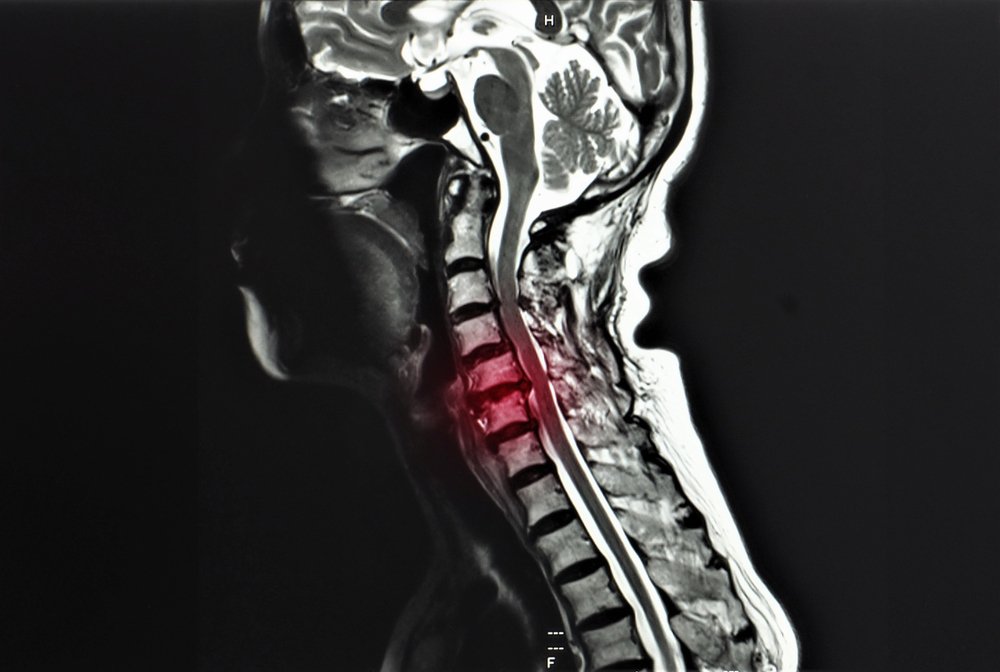

Understanding How Cervical Radiculopathy Could Affect Your Insurance Payout

Cervical radiculopathy is another name for a pinched nerve in the neck. When there is damage or inflammation of a nerve in your cervical spine, it can cause significant pain and impairment. Cervical radiculopathy from a traffic accident can cause:

The concerns related to a pinched nerve can also go beyond your neck. It may affect the shoulder, arm, and hand, too.

Treatment Required for Cervical Radiculopathy from a Traffic Accident

According to Current Reviews in Musculoskeletal Medicine, the treatment necessary for cervical radiculopathy can vary from conservative management of pain to spinal surgery. There is no way to know initially what type of treatment a pinched nerve in the neck may respond to and what it will take to recover from this injury. Possible treatment plans could include: